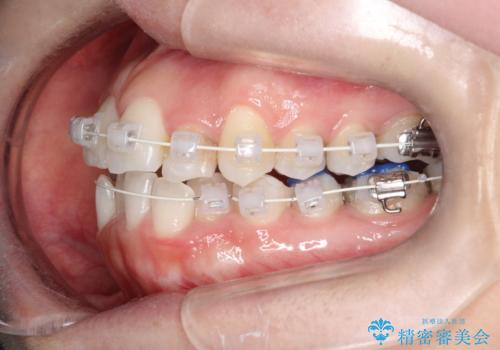

【ワイヤー矯正】前歯の凸凹を非抜歯で治療

- 前歯の凸凹を主訴に来院されました。

側方拡大にてスペースを作ることにより綺麗に前歯を並べることができました。

前歯の凸凹がある場合は治療計画を立てる上でスペースをどのように作るかが重要になります。

今回の場合は主に側方拡大でスペースの確保を行いました。